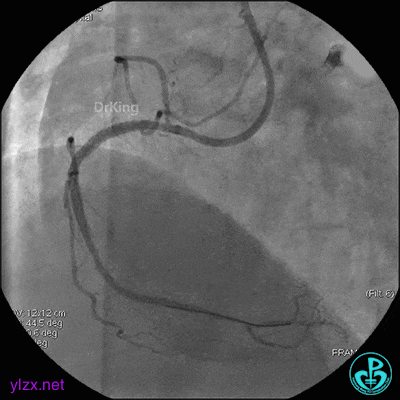

4 急诊冠脉造影

左主干轻度狭窄,左主干到前降支近端钙化影明显。前降支开口严重狭窄,近端闭塞。粗大回旋支轻度狭窄。

右冠脉无严重狭窄,右冠脉没有给前降支提供逆向供血。